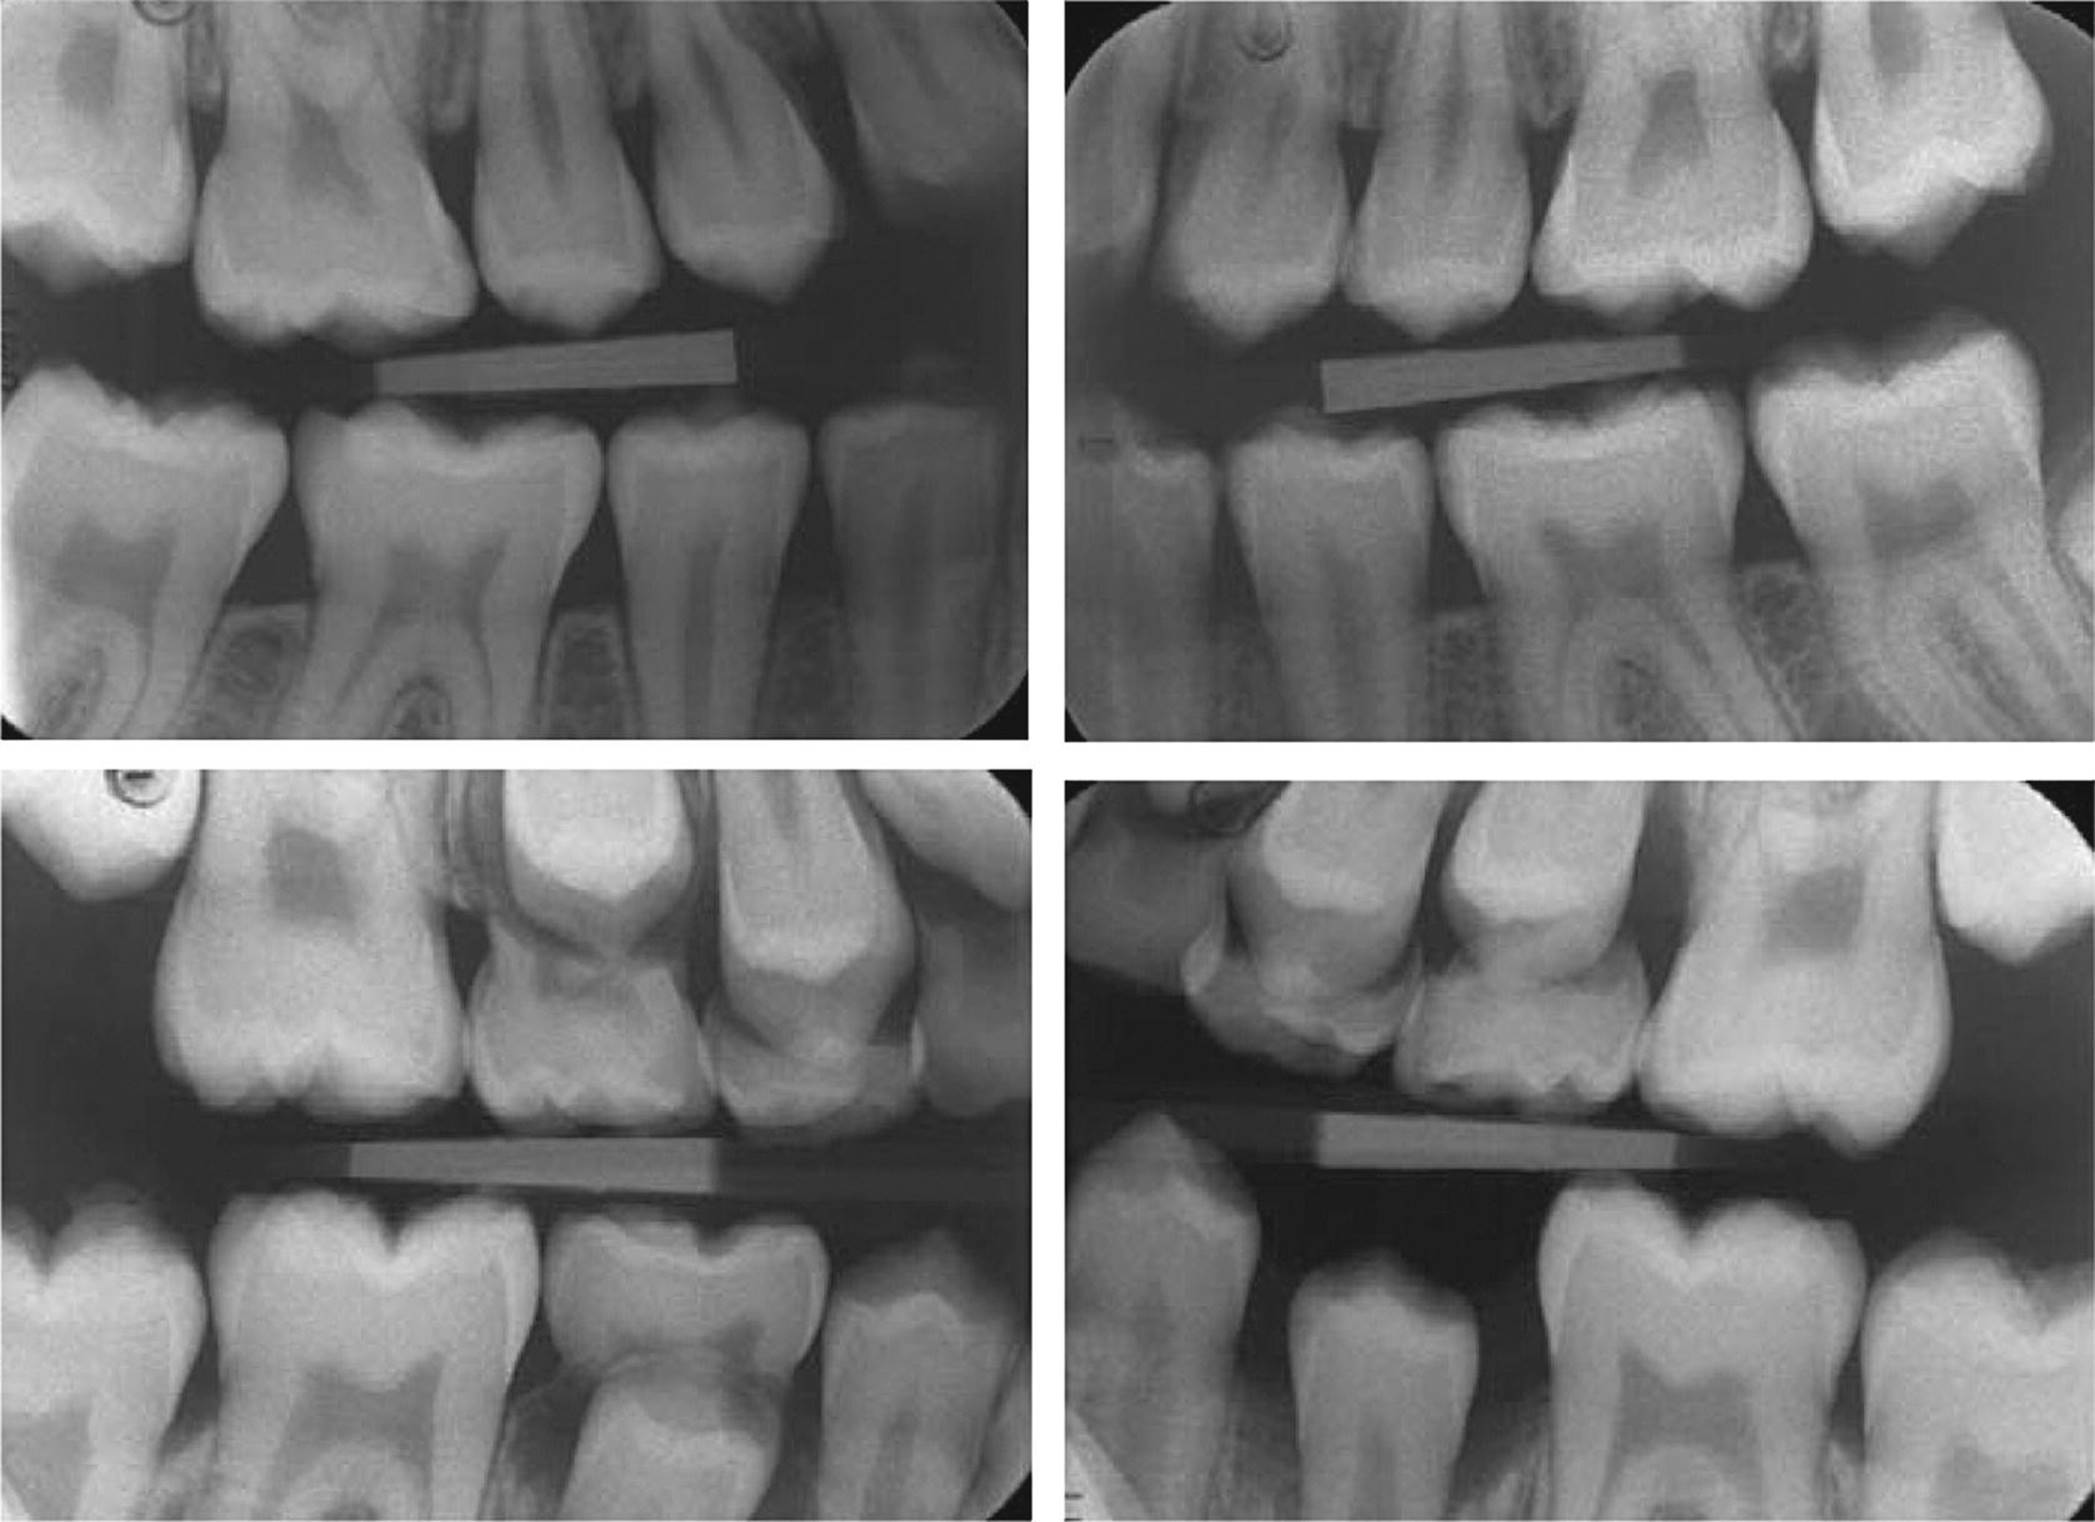

Approximal surfaces

Radiographic examination is the most commonly used method for detecting and assessing caries lesions on approximal surfaces with adjacent contacting surfaces. The early, noncavitated lesion on these surfaces is, however, not possible to detect in the radiographic image [9] and usually not from direct visual–tactile examination either. It is important to bear in mind that the proportion of false‐positive diagnoses from bitewing radiography is relatively high in low caries prevalence populations. Details on the validity of radiographic caries diagnosis are described in Chapter 8.

For an approximal caries lesion contacting a neighboring tooth, the border between nonoperative and restorative treatment is the presence of an obvious clinical cavity on the tooth surface. This diagnostic decision is therefore crucial. However, on this matter the radiograph does not give straightforward information. An example of this is shown in Figure 12.7, where only one of two lesions with similar radiographic appearance had a clinical cavity. Studies comparing the radiographic and clinical appearance of approximal lesions in children and young adults report great variation. The percentage of clinical cavities of surfaces with radiolucencies in the outer half of the dentin varies between 41 and 100%, the median (mean) values being 78% [12–18]. The most likely reasons for this variation are different methods used to record the presence of a cavity, different depths of the lesions investigated, and different populations with different caries activity in the various studies. It is obvious, however, that the deeper the lesion, the more likely is cavitation.

Figure 12.7 Caries lesions on distal surfaces of two mandibular second premolars: both radiographs (a and c) showed radiolucency in outer dentin, but during cavity preparation, a clinical cavity was observed only in one of them (b).

Some clues are useful to assess the probability of the presence of a cavity. Cavitation was more frequently found in A2 and A3 lesions (Figure 12.2b) in individuals with high caries activity than in those with lower caries activity [14]. Cavitated lesions were found more frequently in surfaces with gingival bleeding [19,20]. Tooth separation will allow gentle probing to assess the presence of a cavity. The use of an impression of the approximal surface can be helpful for diagnosing borderline cases [14,17,20]. Admittedly, we lack a simple and valid method for assessing the presence of a cavity on the approximal surface contacting a neighboring surface.